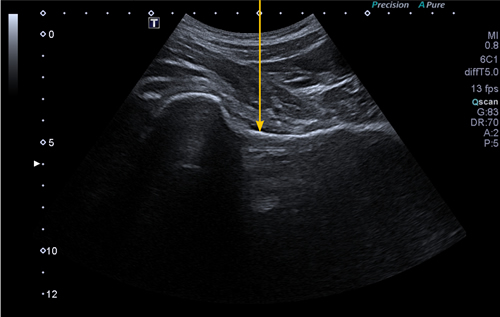

Figura 1

Material y método: Estudio observacional retrospectivo sobre cohorte de pacientes con coxartrosis sintomática, tratados mediante viscosuplementación intrarticular ecoguiada de cadera con dos tipos de inyección única de ácido hialurónico. Su eficacia fue evaluada de acuerdo con las escalas WOMAC y EVA a los 6 y 12 meses.

Material and method: Restrospective observational study on a cohort of patients with symptomatic hip osteoarthritis, treated by ultrasound-guided intra-articular viscossuplementation with two types of single injection of hyaluronic acid. Its efficacy was evaluated according to the WOMAC and VAS scales at 6 and 12 months.